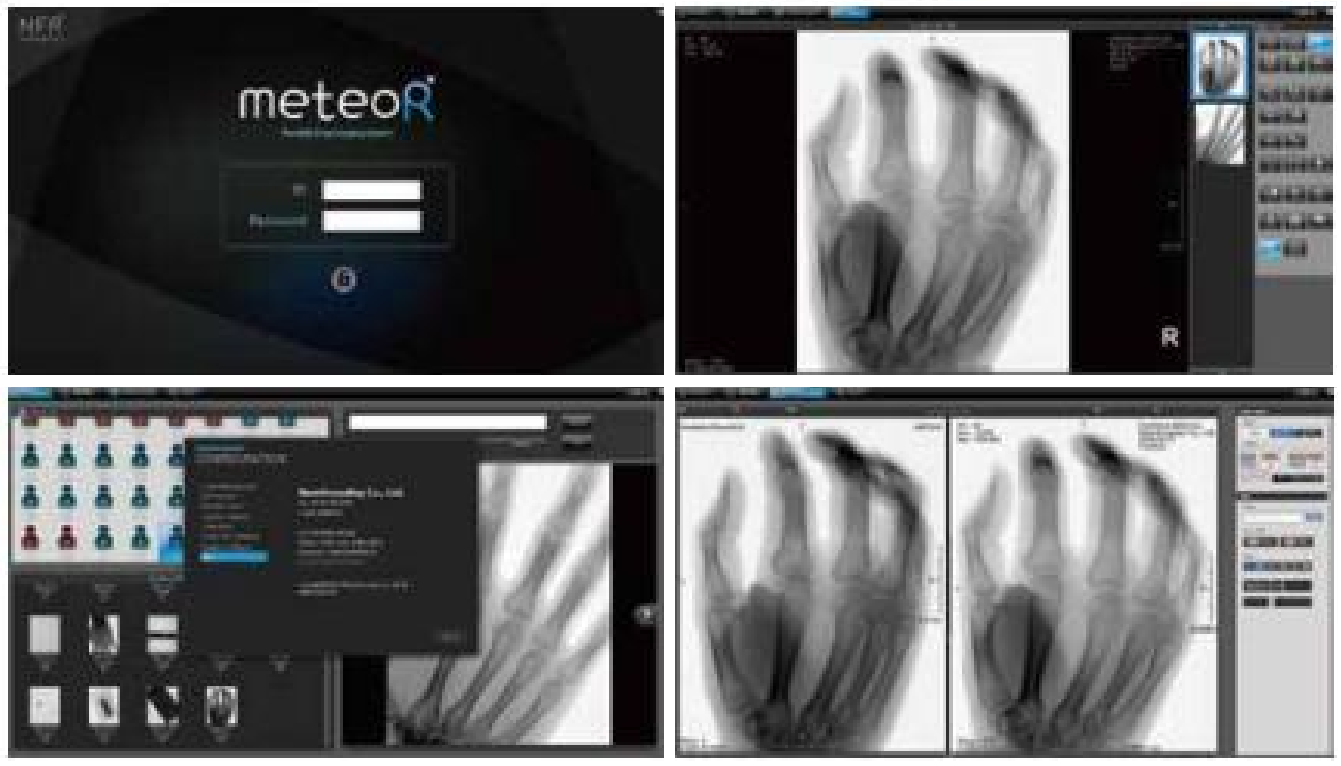

卓越的影像处理技术

康达 C 臂致力于实现对临床用户的长期承诺,立志成为产品技术、客户满意度等方面最成功的 C 形臂服务商。

拥有高精尖技术的 CMN100,以其迷人的设计、领先的技术和非凡的性能成为便携式 mini-C 的代表产品,在手足外科临床上获得高度的评价和认可。

专业图像降噪算法,使得透视影像媲美专业 DR 图像

图像边缘及对比度强化功能,随时调节图像效果

无失真无畸变成像

与复杂而庞大的光学镜头组的影像增强器不同的是,平板探测器具有明显的尺寸和重量优势。

此外,在以影像增强器为基础的成像中,在信号转化链中的很多环节均会有损失和失真。

作为对比,平板具有的直接、简短的信号转换路径,没有光学本质的变化,所以平板的图像从边缘到边缘是平整、一致的,被摄物体 1:1 成像,从根本上消除了光学镜头所固有的畸变,图像完全无失真。

支持医院信息网络建设

系统可以支持 USB、以太网及 WIFI 连接,轻松实现医院影像信息的网络化传输; 支持 DICOM 3.0 协议(发送、存储、打印及工作列表),无缝融入数字化医院网络。